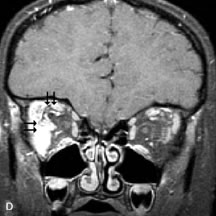

Inflammatory and Lymphoproliferative Lesions

Inflammatory conditions of the orbit, both idiopathic (inflammatory pseudotumor) and those of known causes, have been found to be hypointense to fat and isointense to muscle on Tl-weighted studies and isointense or slightly hyperintense to fat on T2-weighted images (Fig. 21).50,64,69 The more fibrous or sclerosing varieties have less signal intensity on T2-weighted images. Marked enhancement is seen in pseudotumor infiltrates after gadolinium administration.70 The same signal characteristics are demonstrated in patients with Tolosa-Hunt syndrome, with mass lesions seen in the cavernous sinuses and orbital apices.71

Fig. 21. A. T1-weighted MR scan demonstrates diffuse enlargement of both the superior rectus and levator palpebrae superioris muscles (single arrows). The involvement of the tendinous insertions and preseptal soft tissues (open arrows) as well as lack of involvement of other muscles helps differentiate this entity from thyroid-associated orbitopathy. B and C. Postcontrast fat-suppressed T1-weighted MR scans demonstrate extensive enhancement of the involved muscles as well as the preseptal (open arrows) and perinuscular tissues (double arrows).